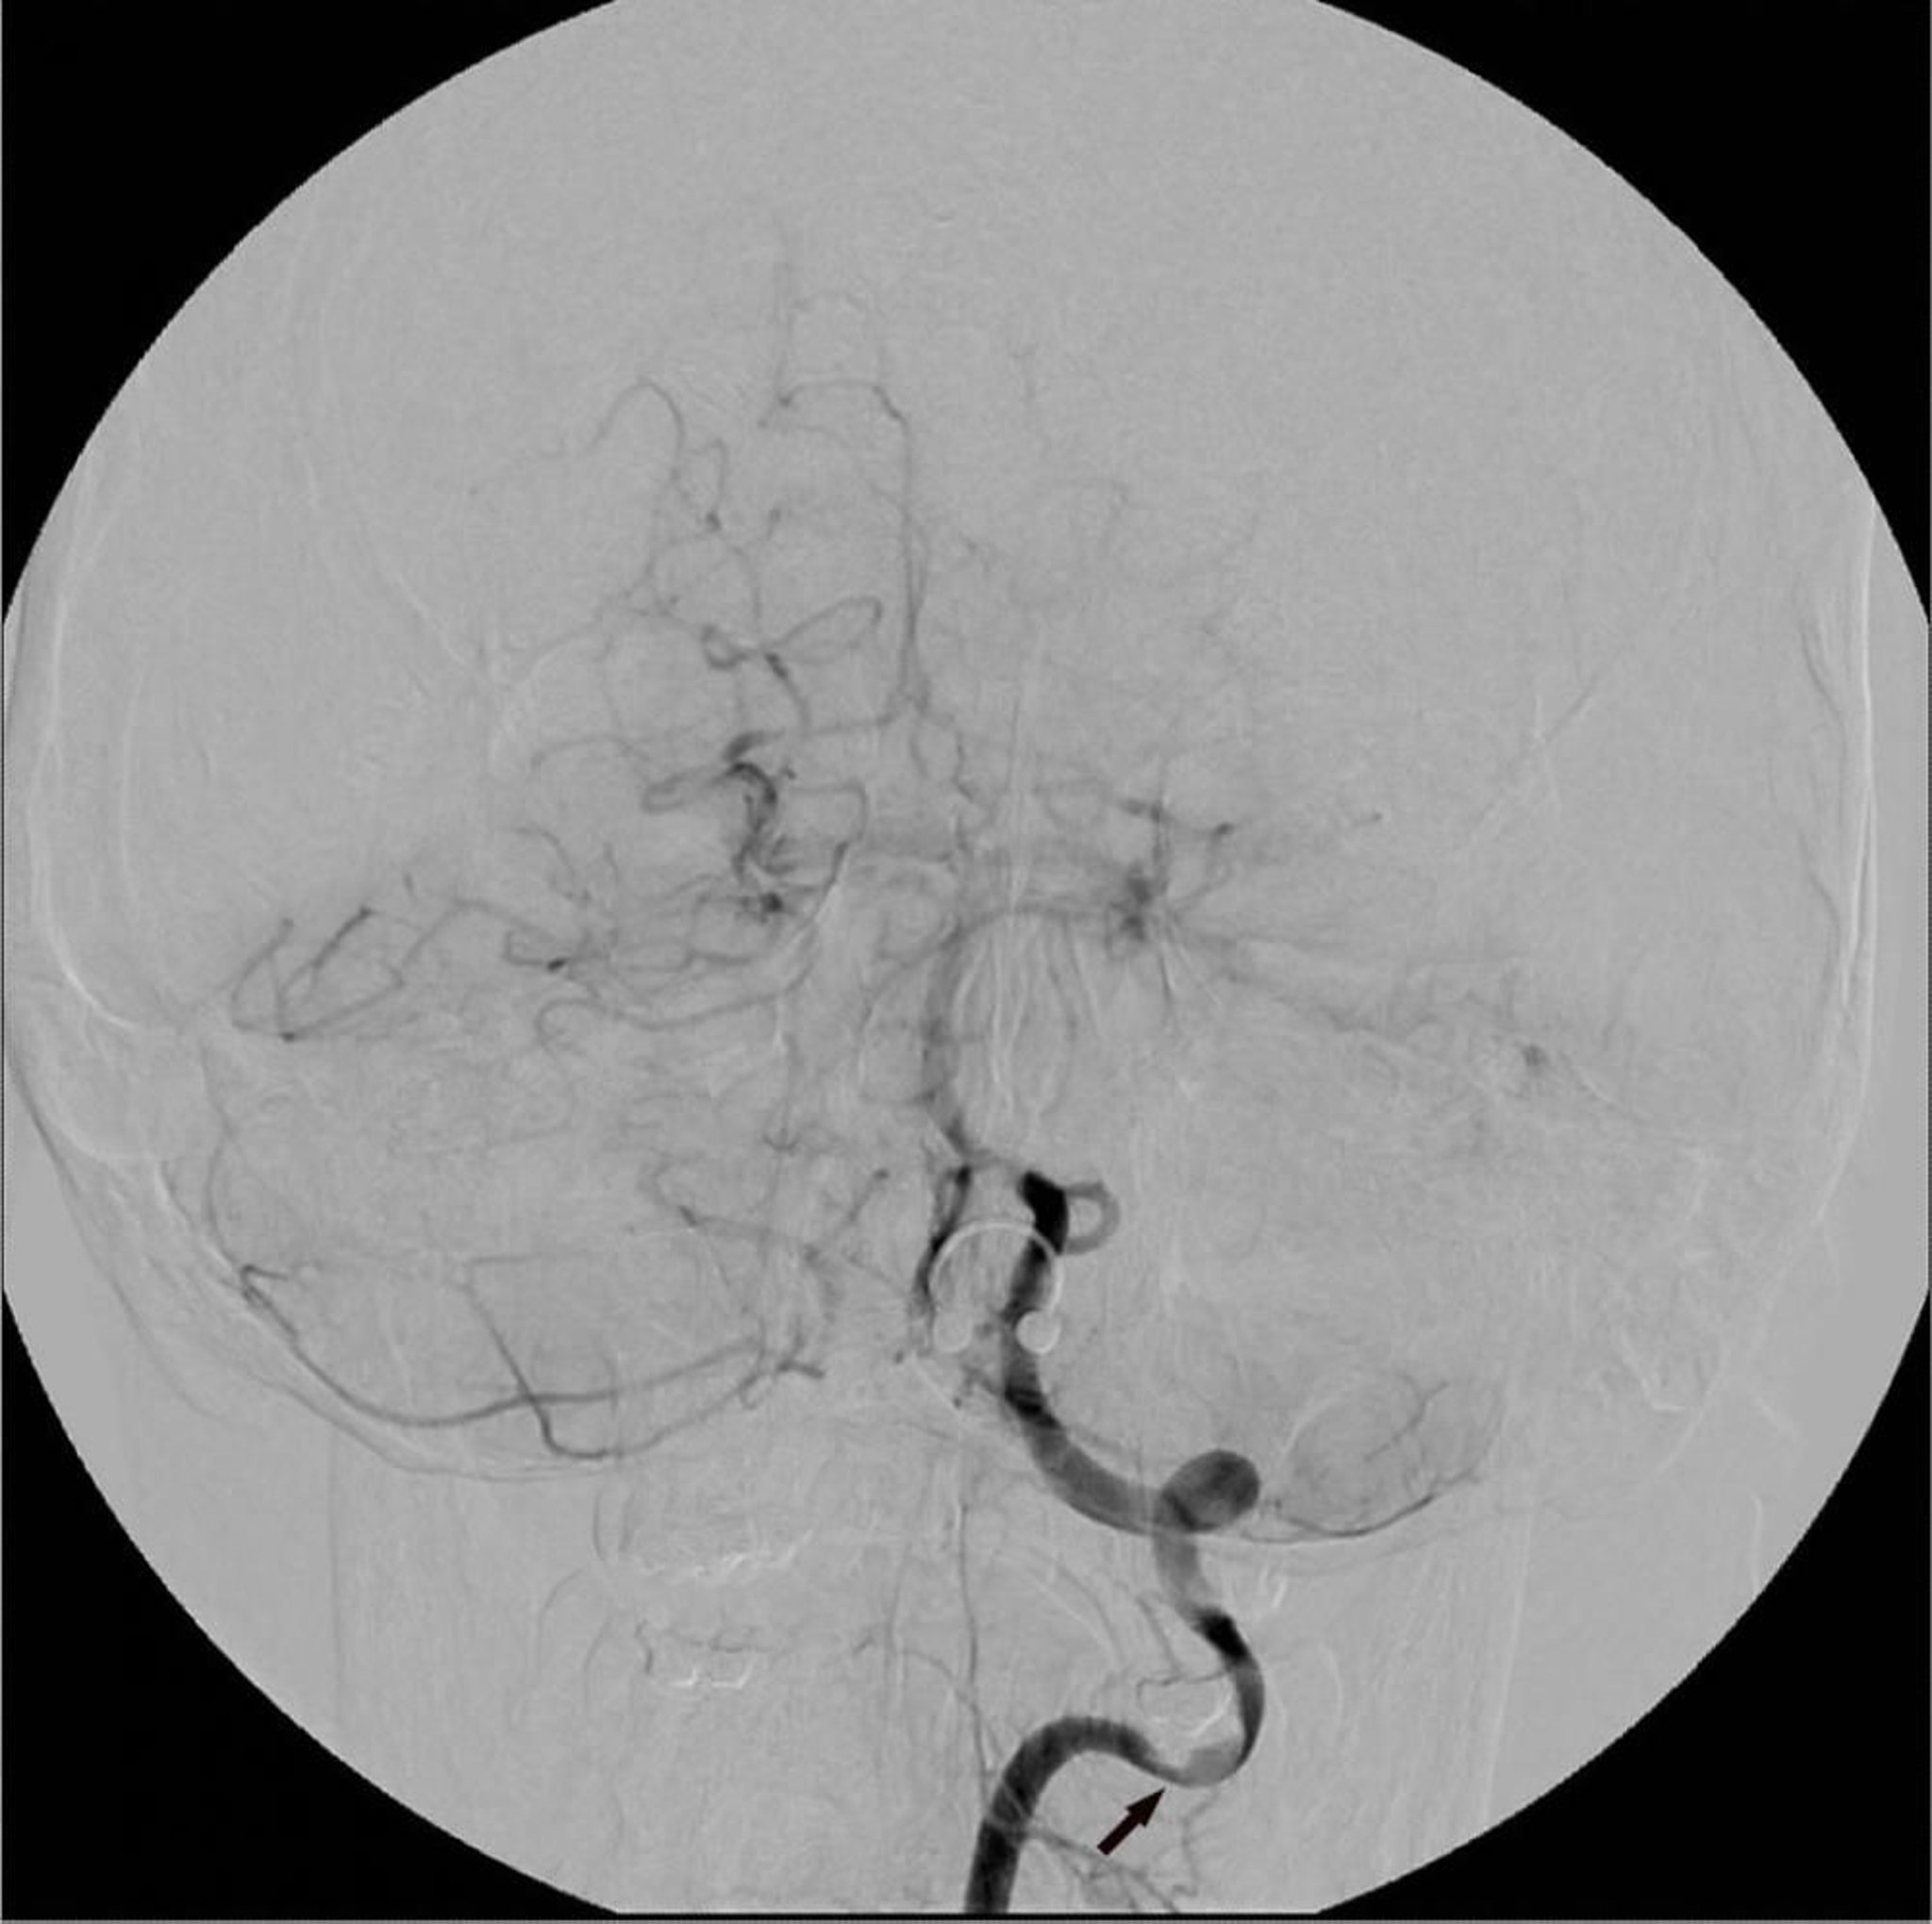

Angiografia a sottrazione digitale

L'angiografia con sottrazione digitale dell'arteria vertebrale sinistra mostra un'area focale di stenosi (freccia).

Image courtesy of Hakan Ilaslan, MD.